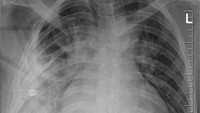

"Rontgen dada lateral awal menunjukkan adanya benda logam tersangkut di bagian tengah dada, dengan bayangan samar di sekitarnya yang mengindikasikan hematoma terlokalisasi kronis yang mengeluarkan cairan, atau fibrosis pasca-trauma, kemungkinan besar akibat luka tusukan pisau pasien," tulis dokter dalam studi kasusnya. (Foto: Journal of Surgical Case Reports)